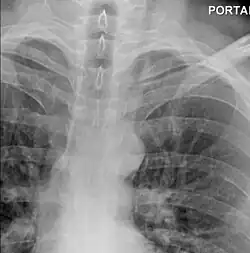

The diagnosis of Boerhaave syndrome is suggested on the plain chest radiography and confirmed by chest CT scan. The initial plain chest radiograph is almost always abnormal in patients with Boerhaave syndrome and usually reveals mediastinal or free peritoneal air as the initial radiologic manifestation. With cervical esophageal perforations, plain films of the neck show air in the soft tissues of the prevertebral space.

Hours to days later, pleural effusion(s) with or without pneumothorax, widened mediastinum, and subcutaneous emphysema is typically seen. CT scan may show esophageal wall edema and thickening, extraesophageal air, periesophageal fluid with or without gas bubbles, mediastinal widening, and air and fluid in the pleural spaces, retroperitoneum or lesser sac.